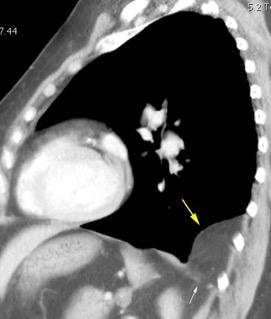

Consolidación por Infarto pulmonar. (TEP)

Tromboembolismo pulmonar Diafragma elevado 20%